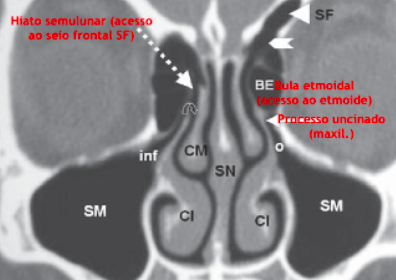

Complexo ostiomeatal (COM)

Componentes